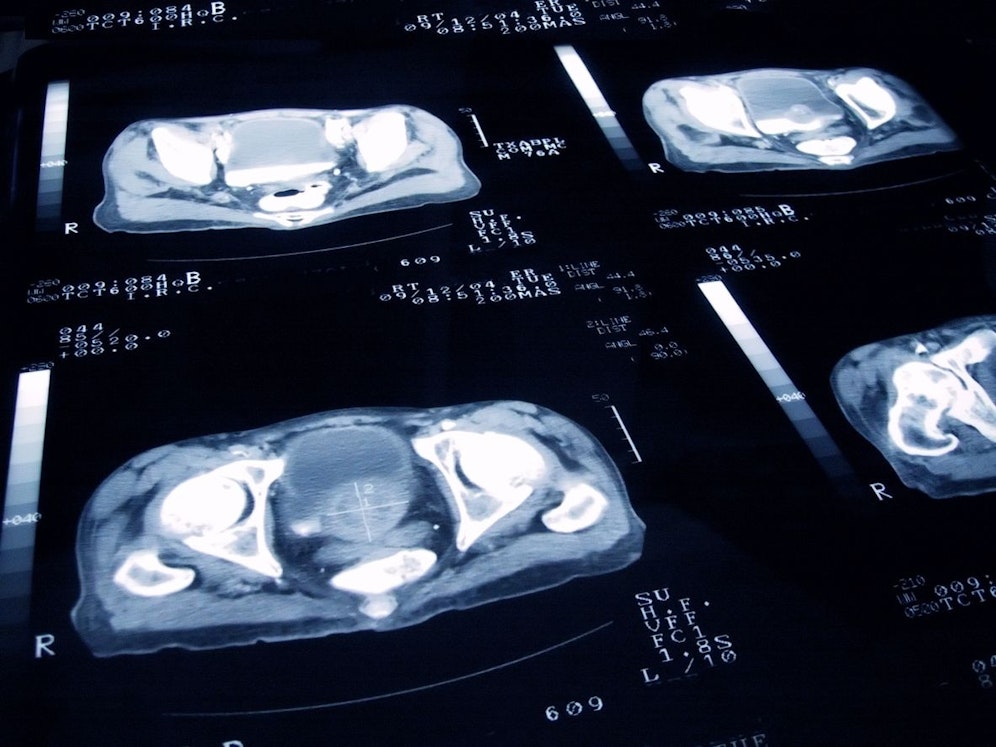

Ärzte der Duke University berichten, dass ein Prostatakrebspatient in den Vereinigten Staaten (USA) nach seiner Diagnose plötzlich mit einem irischen Akzent zu sprechen begann. Dahinter steckt ein äußerst seltenes medizinisches Phänomen.

Dieser seltene Fall des Foreign Accent Syndrome ist einer von nur wenigen, die offenbar eine Folge der Krebserkrankung sind. Die Autoren der Studie berichten in BMJ Case Reports, dass der Mann in den 50ern etwa 20 Monate nach der Diagnose eines metastasierenden Prostatakrebses mit einem "unkontrollierbaren irischen Akzent" zu sprechen begann. Noch rätselhafter ist, dass der Patient keinen irischen Hintergrund hatte und Irland nie zuvor besucht hatte.

Obwohl der Prostatakrebspatient anfangs keine Hirntumore hatte, stellten die Ärzte fest, dass sich im Verlauf der Krankheit einige Hirntumore entwickelten. Vor diesem Hintergrund geht das Team davon aus, dass dieser Fall von FAS tatsächlich darauf zurückzuführen ist.